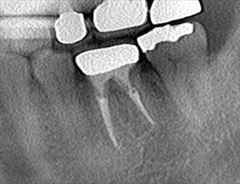

右下大臼歯2本の再根管治療を行いました。2018.05.24

左下第一大臼歯の再根管治療・根管充填を行いました。2018.05.22